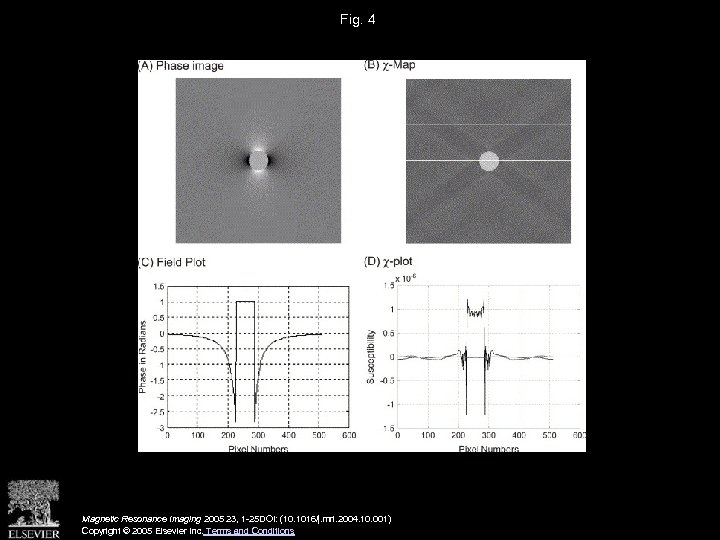

Fig. 4 Magnetic Resonance Imaging 2005 23, 1 -25 DOI: (10. 1016/j. mri. 2004. 10. 001) Copyright © 2005 Elsevier Inc. Terms and Conditions